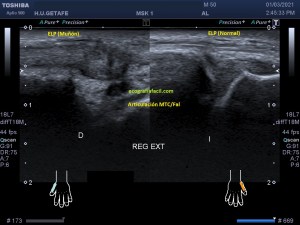

241. Rotura del Extensor Largo del Pulgar. Tercer Compartimento.

Tal como habéis decidido en Insta, voy a proceder a contaros el caso de esta semana. El paciente acude a la cita tarde. No afrontaba la exploración con una actitud positiva, pero la eco te coloca en tu sitio rápido y en este caso, me regaló un caso muy bonito que creo que te va a gustar.

Paciente que acude derivado del traumatólogo por una sospecha rotura del extensor del pulgar. Cuando posicioné al paciente para iniciar la exploración y le hice el interrogatorio habitual, me contó que desde un traumatismo donde se rompió las dos muñecas, tiene una incapacidad para estirar completamente el dedo pulgar a la altura de la interfalángica, no de la metacarpofalángica.

Lo que hice fue lógicamente, dirigir el estudio a los extensores del carpo, cuyo dibujo te dejo a continuación y te lo enlazo con el post donde te hablo de ellos:

1

Exploré el primer compartimento sin ningún tipo de novedad, tanto el Abductor Largo del Pulgar y Extensor Corto del Pulgar. Pasé al compartimento dos, Extensor Radial Largo del Carpo y Extensor Radial Corto del Carpo, ellos dos estaban sin novedad, pero este compartimento guarda una particularidad y una relación especial con el tercero, que es el del Extensor Largo del Pulgardel que está separado por tubérculo de lister, esta relación consiste en la coexistencia de los tres extensores y del paso superior o superficial que el extensor largo del pulgar realiza en un punto sobre el compartimento 2. Es importante que entiendas anatómicamente esta relación y te la enlazo aquí.

Lo que hace el tercer compartimento nada más desplazarnos hacia distal en el corte axial de la muñeca en su cara extensora y donde visualizamos el tubérculo distal separando ambos compartimentos 2 y 3, lo que hace el tercer compartimento, decía, es cruzarse por encima del dos para buscar diagonalmente su paso y su inserción en la cara dorsal del dedo pulgar. Si no entiendes esta anatomía, no vas a poder entender lo que pasa.

Lo que me llamó la atención fue que la parte superficial del segundo compartimento, correspondiente con el extensor largo del pulgar cruzando por encima del compartimento 2, era que estaba muy hipoecogénica y grande, así que una vez comprobado que los dos tendones del compartimento eran normales, y sabiendo que el tercero pasa por encima para cruzarse buscando el primer dedo, lo que hice fue seguir el tercer compartimento y lo que ví era que estaba situado en su lugar junto al tubérculo de lister, proximalmente, que a su cruce por encima del compartimento dos, estaba hipoecogénico y gordo y que ya en la mano, por donde cruza buscando el primer dedo, no estaba o al menos no estaba íntegro.

En este recorrido encontré un muñón, que se observa perfectamente en longitudinal, y que correspondía con el extensor largo del pulgar a la altura de su recorrido.

2

El extensor es claramente visible y palpable, te lo indico, pero tu misma puedes objetivarlo si te observas tu mano y realizas una extensión forzada del primer dedo. Con toda esta descripción, que espero que te haya quedado clara, situando la zona donde el tendón estaba roto (punto rojo), te dejo las imágenes que son muy esclarecedoras, con su anatomía ecográfica para que identifiques cada paso que dí en esta exploración, siempre en función y en estrecha relación con el conocimiento de la anatomía en ese lugar.

3

En esta imagen quiero que te fijes en el segundo compartimento y como el extensor largo del pulgar pasa por encima, los dos tendones del compartimento dos cortados en eje corto y el del tercero, cortado, pero en un corte para-axial. Lo importante es que te fijes en la ecogenicidad de ELP, en la izquierda hiperecogénico, isoecogénico con el segundo compartimento, por tanto normal. En la derecha hipoecogénico y más gordo, patológico.

4

Seguimos avanzando hacia distal, seguimos observando las mismas diferencias en las imágenes comparativas. Imagen justo antes de la rotura.

5

En la rotura el tendón es muy pequeño, pero normal en la izquierda y en la derecha lo es igual de pequeño, pero aplanado y con la pérdida de la ecogenicidad normal.

6

Después de la rotura, avanzando a distal, el tendón retraído, hipoecogénico, mucho más grande que su comparativo contralateral.

7

Corte en eje largo correspondiente a la imagen 6, donde se ve claramente lo que pasa y es definitivo para el diagnóstico final.

8

Comprobar con doppler para ver si hay actividad, que no la hay y es que la lesión no es reciente y esto podría explicar tal circunstancia.

En resumen, desde la imagen 3 a la 8 observas el recorrido ecográfico del tendón extensor del pulgar desde proximal hasta distal, pasando por el foco de rotura y terminando con el muñón en axial y en longitudinal según marcan los pictogramas.

La imposibilidad de poder extender el pulgar quedaba explicada con estos hallazgos. Un caso muy bonito, que espero que te sirva, sobre todo para que veas lo importante de la anatomía en esta técnica de la MSK.

9

Esta imagen final demuestra muy claramente lo que ha pasado y como ha quedado la zona en cuestión. El tendón retraído parece continuarse hacia proximal, filiforme, hasta que llega a otro ensanchamiento hipoecogénico, en relación con el muñón proximal.